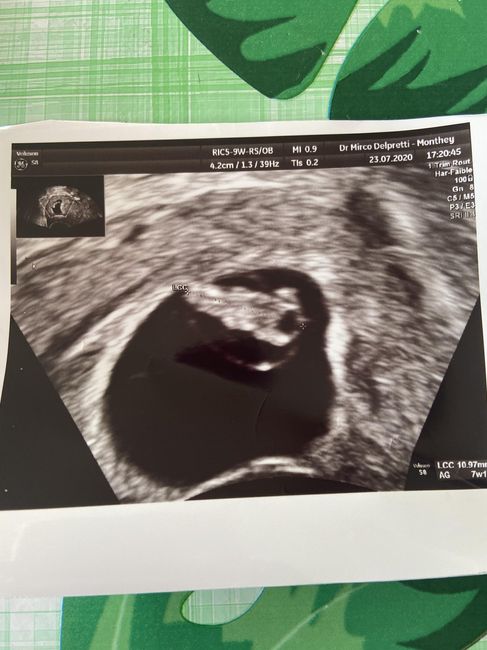

Ciao ragazze,ieri sera ho preso un altro brutto spavento. Ho avuto perdite di sangue molto forti, sono andata al pronto soccorso, ero molto spaventata... fortunatamente il mio cucciolo/a era lรฌ e il...